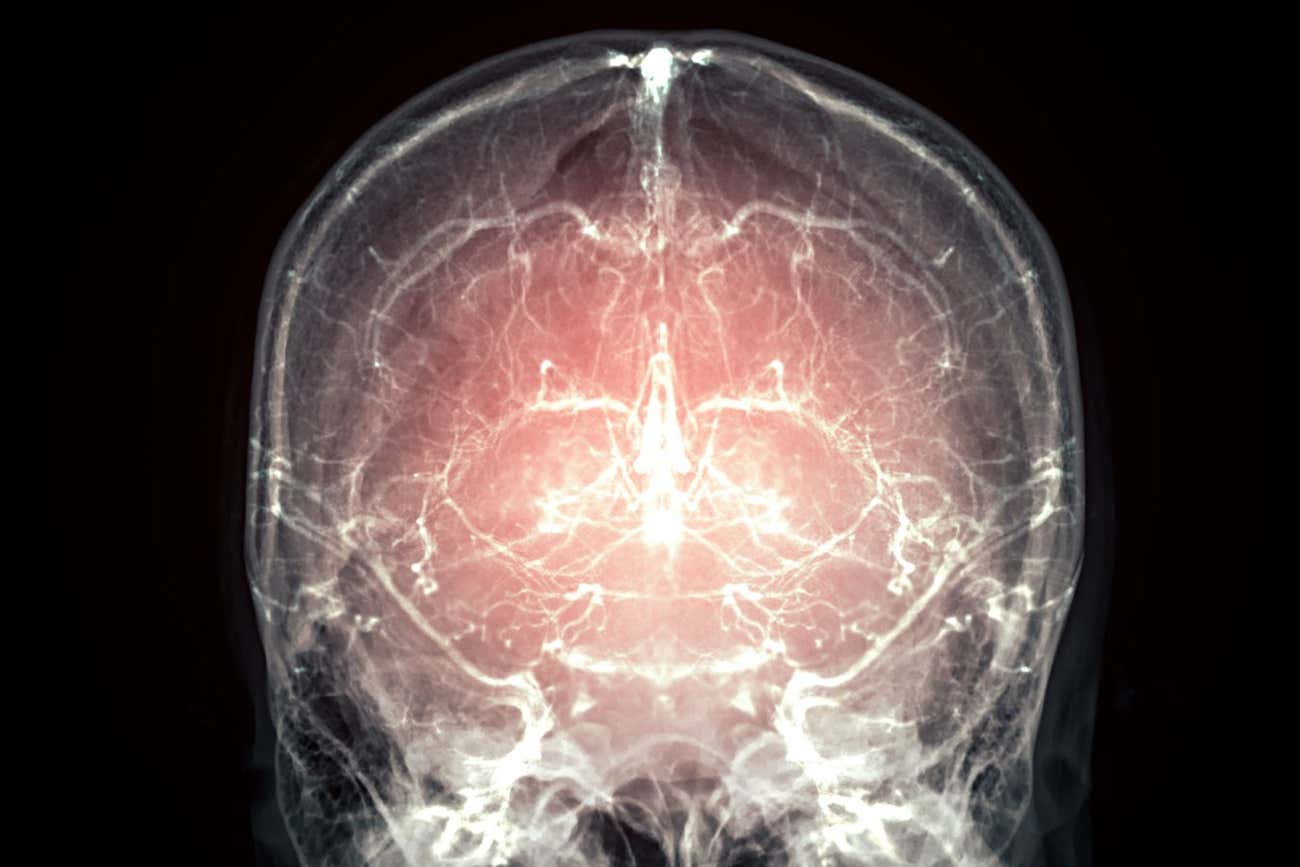

哺乳动物大脑保存技术取得突破,死后复生迎来曙光

研究人员成功冷冻了一颗猪脑,不仅将其细胞活动完整锁定,还实现了极低的损伤。部分专家坚信,这项技术同样适用于绝症患者,通过重建意识,让他们得以“延续生命”。

目前,一项全新的技术已成功实现了完整哺乳动物大脑的保存,并准备向绝症患者开放。该技术的初衷是完整保留所有的神经信息,以便在未来的某一天,能够据此重建大脑原主人的意识。

“捐献者需要为了科学研究献出自己的大脑和身体,”鲍里斯·弗罗贝尔介绍道,他在旧金山的奈克通公司工作,这是一家专门研究记忆保存的科研机构。“而我们公司所提供的服务,是让他们的躯体和大脑能够近乎永久地存放下去。我们希望在未来的某个时刻,人类能够读取大脑中的信息并重塑个体,从实质上让他们继续原本的生活。”